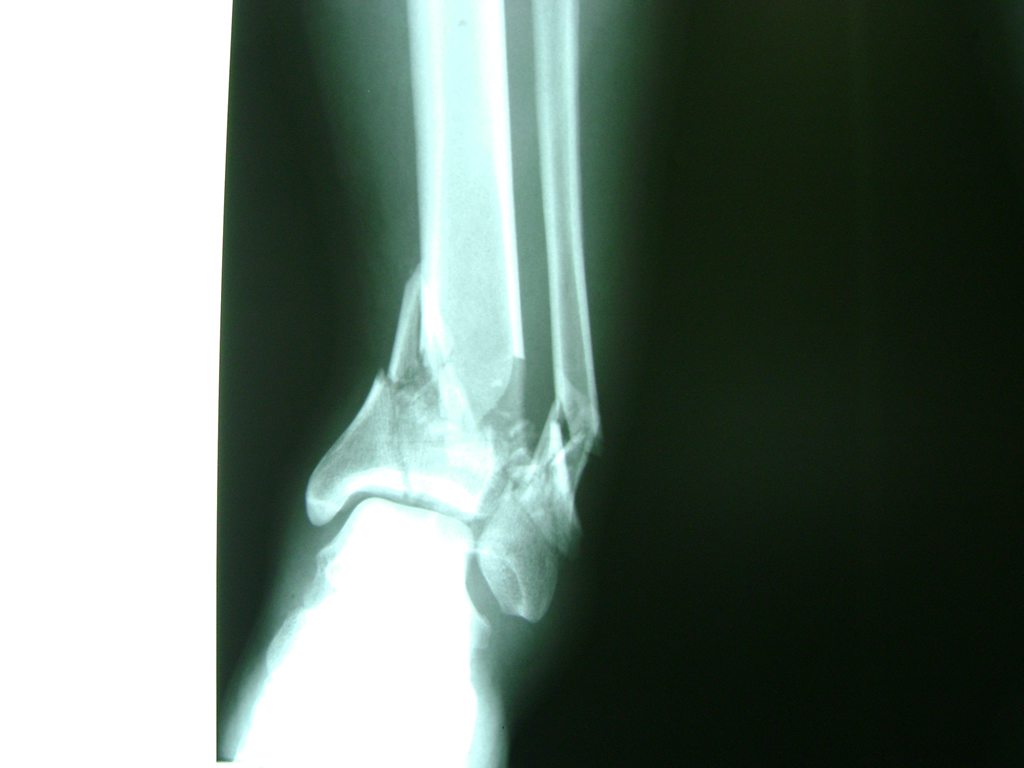

Una fractura de tobillo es la rotura de uno o más de los huesos del tobillo. Estas fracturas pueden ser:

- Parciales (el hueso está sólo parcialmente fisurado, no del todo).

- Completas (el hueso está perforado y está en 2 partes).

- Producirse en uno o ambos lados del tobillo.

Algunas fracturas de tobillo pueden requerir cirugía si:

- Los extremos de los huesos están desalineados entre sí (desplazados).

- La fractura se extiende hasta la articulación del tobillo (fractura intra-articular).

Cuando se necesita cirugía, es probable que esta implique el uso de clavijas de metal, tornillos o placas para sostener los huesos en su lugar mientras la fractura se consolida. Los elementos de soporte pueden ser temporales o permanentes.